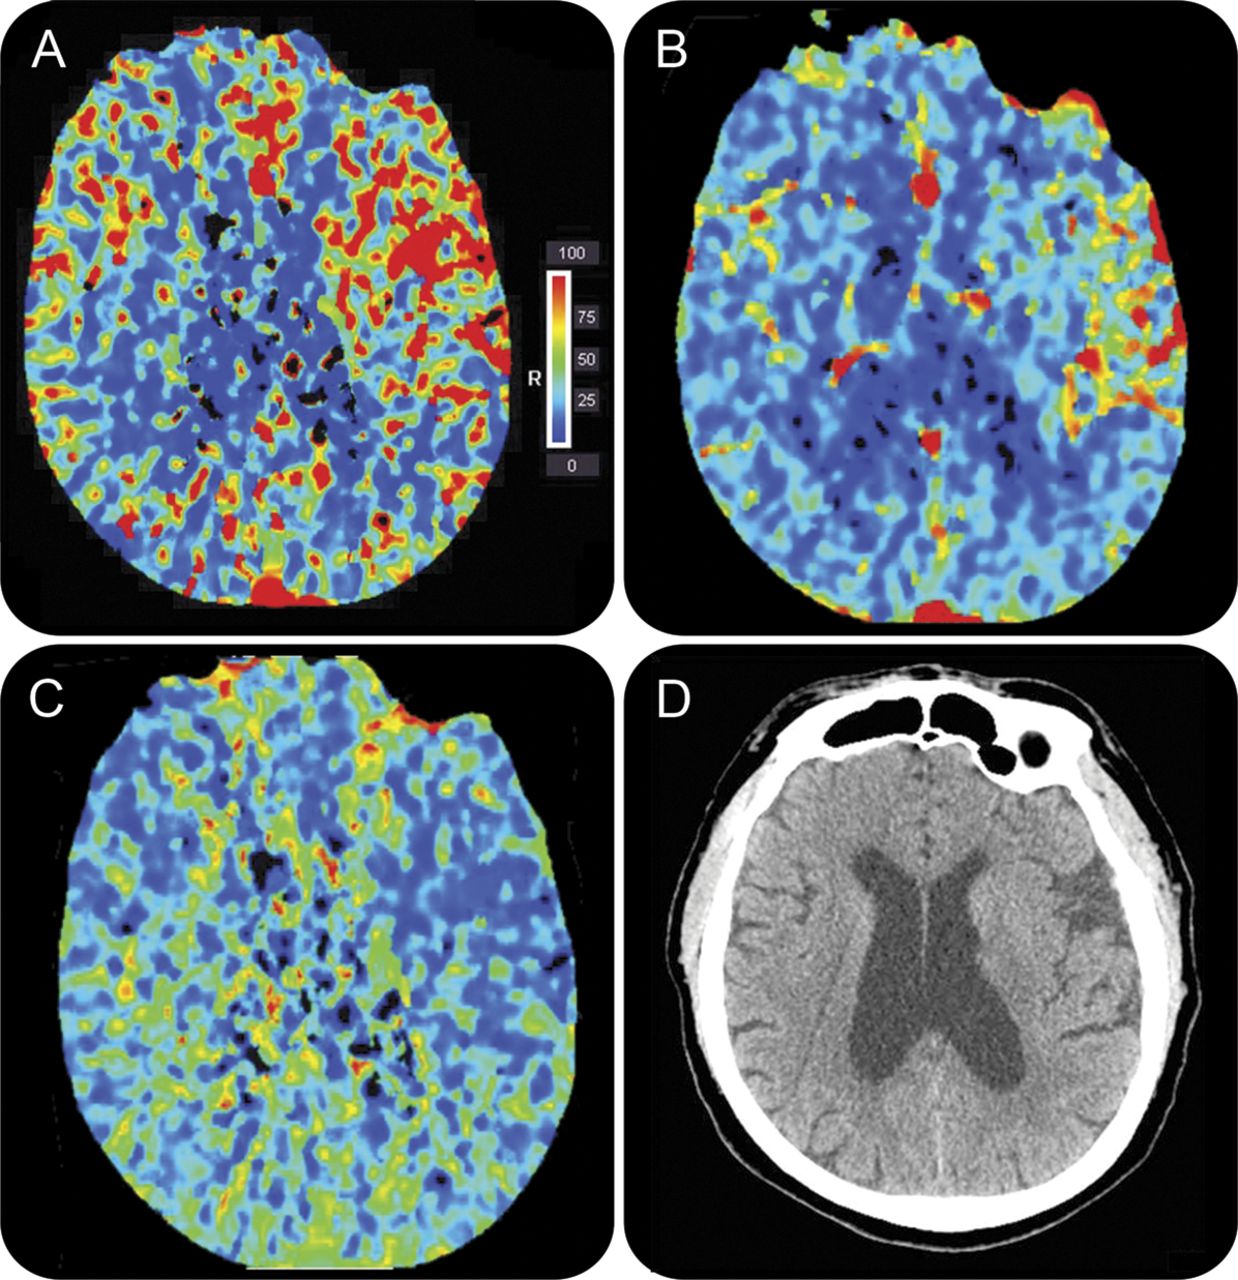

CT灌注左颈动脉内膜切除手术后1天完成

CT显示左侧大脑中动脉分布相对脑血流量增加(A)、相对脑血容量(B),增加和减少平均运输时间(C)发现符合脑hyperperfusion综合症后血管再生。41 CT显示没有出血和水肿(D)。